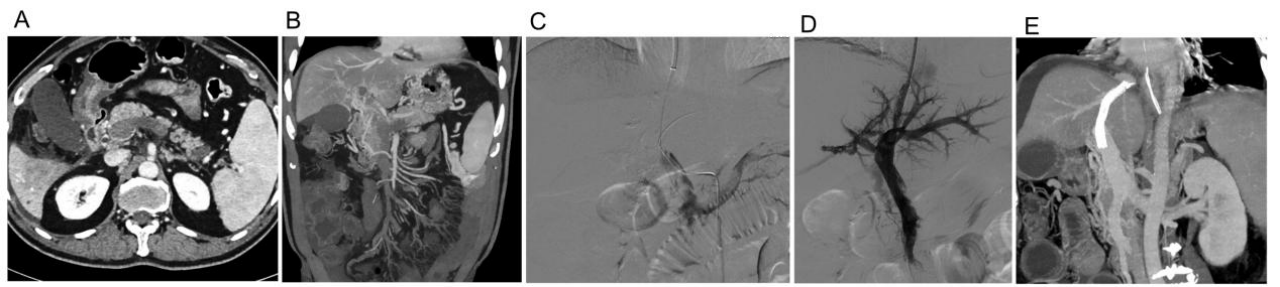

针对急性门静脉血栓患者,团队创新性地采用经颈静脉肝内门体分流术入路联合 AngioJet 机械吸栓、导管吸栓及导管溶栓的「三联疗法」。研究数据显示,该技术可快速开通闭塞门静脉、恢复肠系膜灌注,且未增加出血等并发症风险。专家表示,这一技术突破解决了传统溶栓治疗周期长、效果不确定的难题,尤其适用于危重患者的紧急救治。